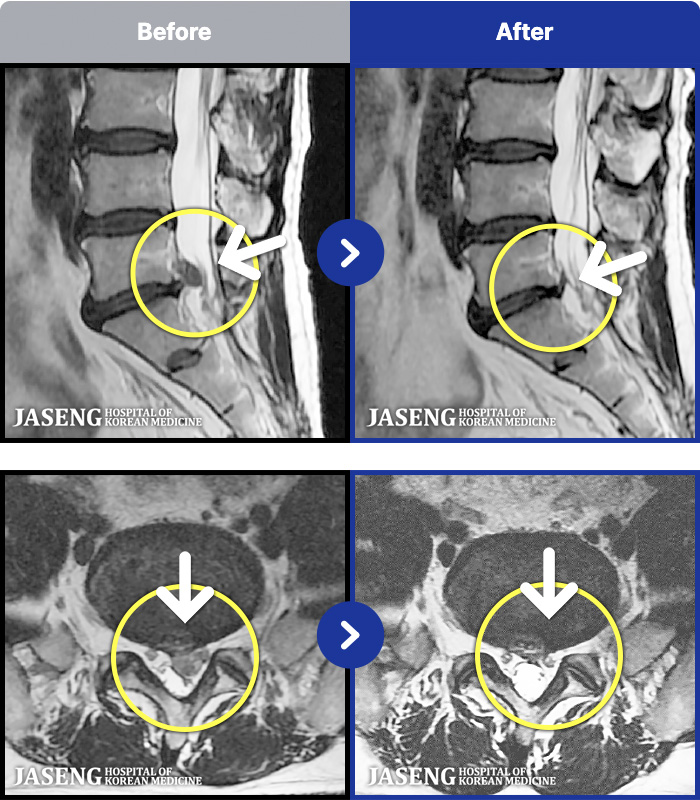

MRI ġ

1,299 MRI ũ ʸ Ȯϼ.